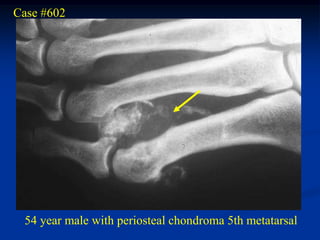

Case #602

54 year male with periosteal chondroma 5th metatarsal